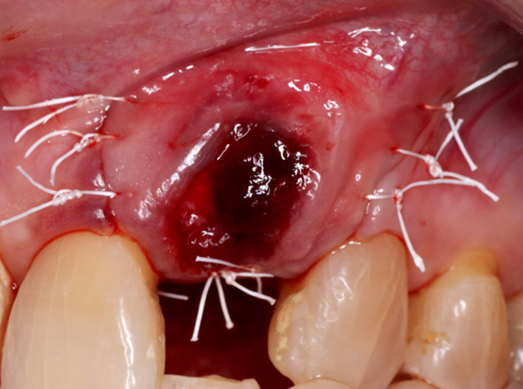

Nossa proposta é relatar o caso clínico da paciente M. S., que procurou a clínica do Curso de Especialização de Implantodontia da Universidade Paulista (Grupo Apoio) devido à condição do dente 22. Uma vez que a destruição periodontal era muito extensa, incluindo o ápice dental, foi indicada a exodontia do dente 22. Buscando reduzir o número de procedimentos cirúrgicos e o tempo necessário para a finalização do caso, foi realizada a reconstrução óssea imediatamente após a remoção do dente. Foi realizada a técnica de Regeneração Óssea Guiada (ROG) com membrana não absorvível de PTFE denso (Cytoplast), associada a enxerto ósseo xenógeno composto por 75% de hidroxiapatita e 25% de colágeno do tipo I (Extra Graft) (Vídeo 1 e Figura 3).

A escolha da técnica acima fundamenta-se no alto nível das evidências científicas associadas ao uso da associação da Regeneração Óssea Guiada (ROG) + substitutos ósseos xenógenos (Sanz-Sánchez et al., 2015), que garantem previsibilidade e bons resultados clínicos conforme demonstrado na Figura 8.